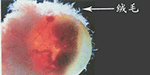

三、胎儿绒毛亲子鉴定:

孕妇怀孕10周以后可以通过绒毛活检术提取绒毛来做鉴定,胎儿绒毛取样时间理论上在孕妇怀孕满8周至12周,但在12周进行取样会较为稳定。

孕妇怀孕10周以后可以通过绒毛活检术提取绒毛来做鉴定。

胎儿绒毛取样时间理论上在孕妇怀孕满8周至12周,但在12周进行取样会较为稳定。